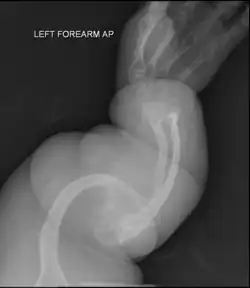

Collagen is fatally defective at its C-terminus.[5]: 1512 Most cases result in death shortly after birth, or within the first year of life, due to respiratory failure. Another common cause of death is intracranial bleeds from skull fractures present at, or sustained during or shortly after, birth.[5]: 1511 In many cases, the newborn already has multiple broken bones at the time of birth. Type II infants also exhibit severe respiratory problems and have severely deformed bones. Sixty percent of infants die less than 24 hours after being born, and survival after the first year is extremely unlikely and normally requires mechanical ventilation.[57] In the rare cases of infants who survive their first year of life, severe developmental and motor delays are seen; neither of two infants studied in 2019, both aged around two years, had achieved head control, and both required a ventilator to breathe.[58]

Type II is also known as the "lethal perinatal" form of OI,[59] and is not compatible with survival into adulthood.[57] Due to similarly severely deformed bones, sometimes infants with severe type III are wrongly initially classified as type II; once long-term survival is shown, they are considered as having type III instead.[5]: 1511 [60]

OI type III causes osteopenic bones that fracture very easily, sometimes even in utero, often leading to hundreds of fractures during a lifetime;[24] early scoliosis that progresses until puberty; dwarfism (a final adult height frequently less than 4 feet or 120 centimetres); loose joints; and possible respiratory problems due to low rib cage volume causing low lung volumes.[5]: 1512